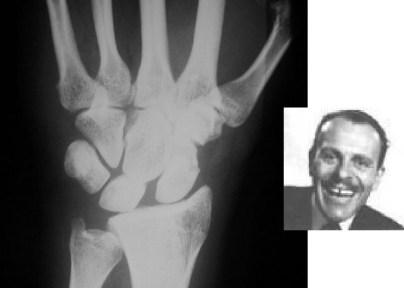

SIGNO DE TERRY THOMAS

Ensanchamiento del espacio articular entre el escafoides carpiano y el semilunar visible en la luxación escafo-semilunar. Recibe el nombre del actor británico Terry Thomas por el parecido de la imagen radiográfica con el de la dentadura del actor.

Otro ejemplo de este signo, a la izquierda. A la derecha, fotografía del célebre actor con su característica dentadura con separación de los incisivos superiores.